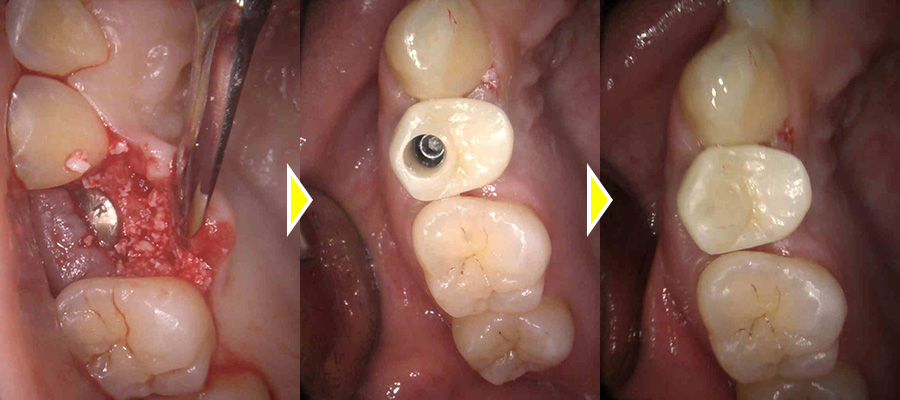

右上歯がない部分をインプラントで修復した症例

こちらの患者さまは、右上歯がない部分に歯を入れたいとの主訴で来院されました。

他院でインプラントを行っていないとの事で断られ、インプラントが可能か相談に来られました。

他の治療法で入れ歯、ブリッジの選択肢の説明も行いましたが、他の歯への負担が気になるとのことだったので、インプラントでの治療をご希望され、行うことになりました。

抜歯後の骨の治りが悪く、中に骨ができていない部分もあったため、小規模な骨造成も同時に行いました。

2回法により施術を、行い、3ヶ月後には歯茎も綺麗に回復しておりました。

二次オペを行いしっかりとした固定も得られていた為、型取りを2度行い上部に歯を作成しました。

術後は欠損部位の見た目の改善により、審美的に大変満足していただき、また、機能的な面でも硬いものもしっかり噛むことができ、機能的な面でも大変満足していただきました。